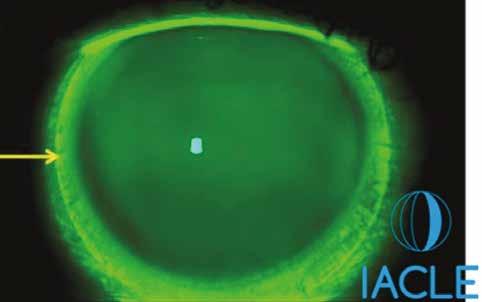

Excesiva presión del borde del lente sobre la conjuntiva.

En ocasiones se ha observado la conjuntiva rasgada, debido a un borde de lente filoso o dañado. El teñido conjuntival puede ocasionarse por un borde cerrado de un lente o posiblemente por presión mecánica de la parte de la zona de apoyo del lente. Cuanto mejor se alinee el lente con la forma escleral, mejor será la dispersión de presión, que puede disminuir la cantidad de teñido conjuntival. Esto tiene lugar más comúnmente en el meridiano horizontal. Si el teñido está presente por debajo del área de la zona de apoyo, ello parece implicar que el meridiano horizontal es habitualmente más plano, ocasionando más compresión mecánica en el meridiano horizontal. Los lentes asimétricos pueden ser los indicados para evitar esta situación. Si el teñido sobrepasa los bordes del lente escleral, lo cual puede suceder en particular en lentes esclerales más pequeños, la etiología del teñido puede deberse a problemas de exposición y por lo tanto de sequedad. En el uso de los lentes GP corneales, se ha demostrado que la sequedad en las partes nasal y temporal inmediatamente adyacentes al borde del lente puede llevar a niveles significativos de teñido corneal (teñido en las horas 3 y 9). Con lentes esclerales podría ocurrir el mismo efecto en la conjuntiva. Cubrir esta área con la zona de apoyo del lente escleral por medio del uso de un diámetro mayor de lente podría solucionar el problema.